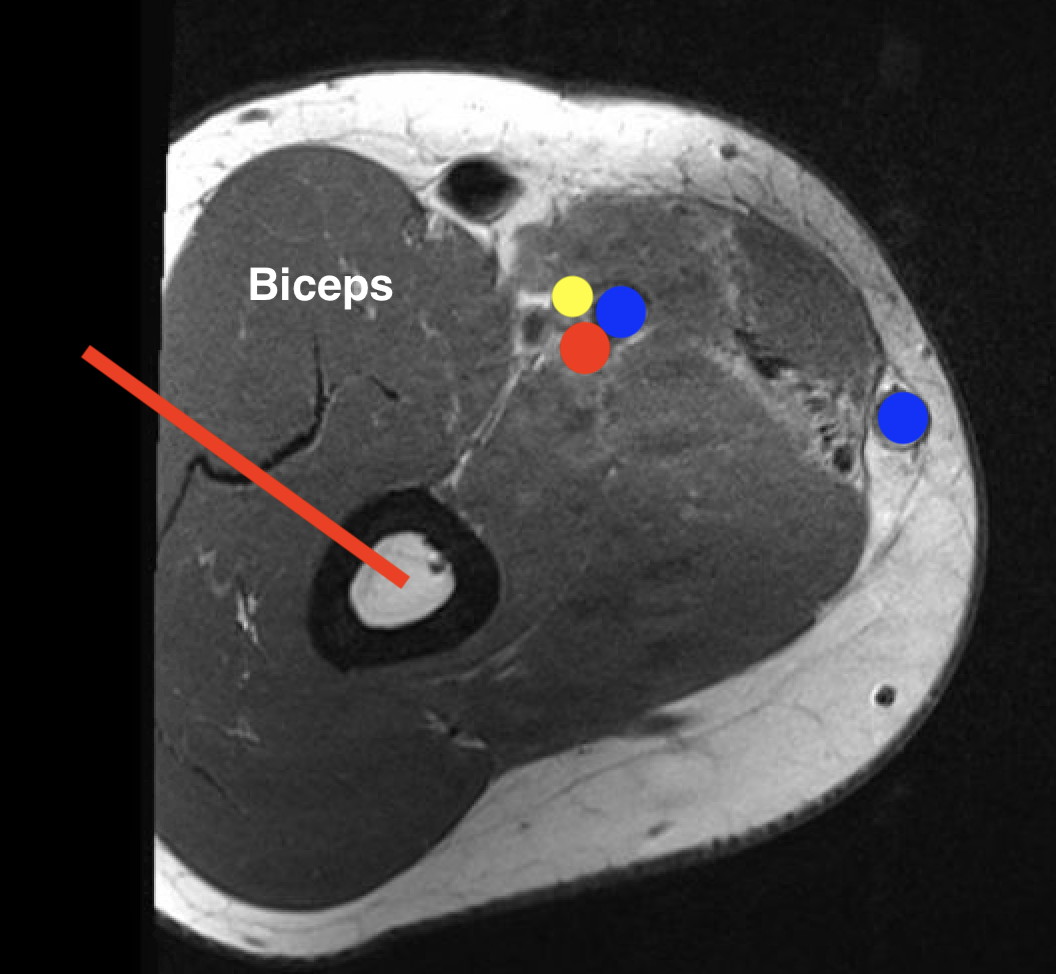

2.  Shaft

- modified Henry

- lateral approach

- proximal: through deltoid

- distal: posterior to biceps, through brachialis

OS HumerusHumerus biopsy 2